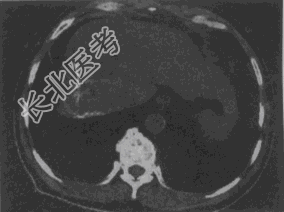

- 单项选择题女,56岁, 腹胀、双下肢水肿、乏力、食欲缺乏,影像所见如下图, 最可能的诊断是

A、酒精性肝硬化并肝血管瘤

B、血吸虫肝硬化并肝癌

C、肝炎后肝硬化并肝癌

D、局限性脂肪肝

E、原发性肝癌